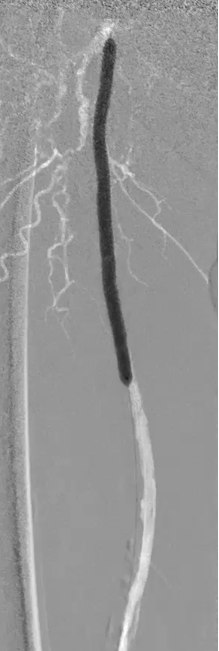

步进造影配合血管腔内超声诊断导管提示:股浅动脉全程、腘动脉、胫腓干动脉血流通畅,未见明显夹层、造影剂外溢,远端未见栓塞,膝下动脉如前。

腘动脉压力:90mmHg,比值0.73(原比值 0.54)

足背动脉压力85mmHg,比值0.69(原比值 0.45)

腘动脉压力:120mmHg,比值0.98 (原比值 0.65)

胫后动脉压力:118mmHg,比值0.96(原比值 0.54)

足背动脉压力:115mmHg,比值0.93(原比值 0.59)